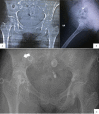

Primary psoas tuberculosis abscess with an iliac bone lytic lesion: a case report

Background: Primary psoas tuberculosis is the presence of "Koch's bacillus'' within the iliopsoas muscle caused by hematogenous or lymphatic seeding from a distant site. Muscular tuberculosis has relatively low prevalence in comparison with other cases of extrapulmonary tuberculosis, which explains the difficulties in establishing the diagnosis.

Case presentation: In this report, we present a challenging diagnostic case of primary psoas tuberculosis in a 38-year-old middle eastern female from southern Syria. The diagnosis was based on the clinical orientation, the observation of pulmonary lesions on the computed tomography scan, and the necrotic signs in the vicinity of the infected area. Despite the misleading primary false-negative results, the final diagnosis was reached after sufficient repetition of tuberculosis-specific testing. The patient was treated with isoniazid-rifampin-pyrazinamide-ethambutol for 2 months, then isoniazid and rifampin for 7 months, with full recovery in follow-up.